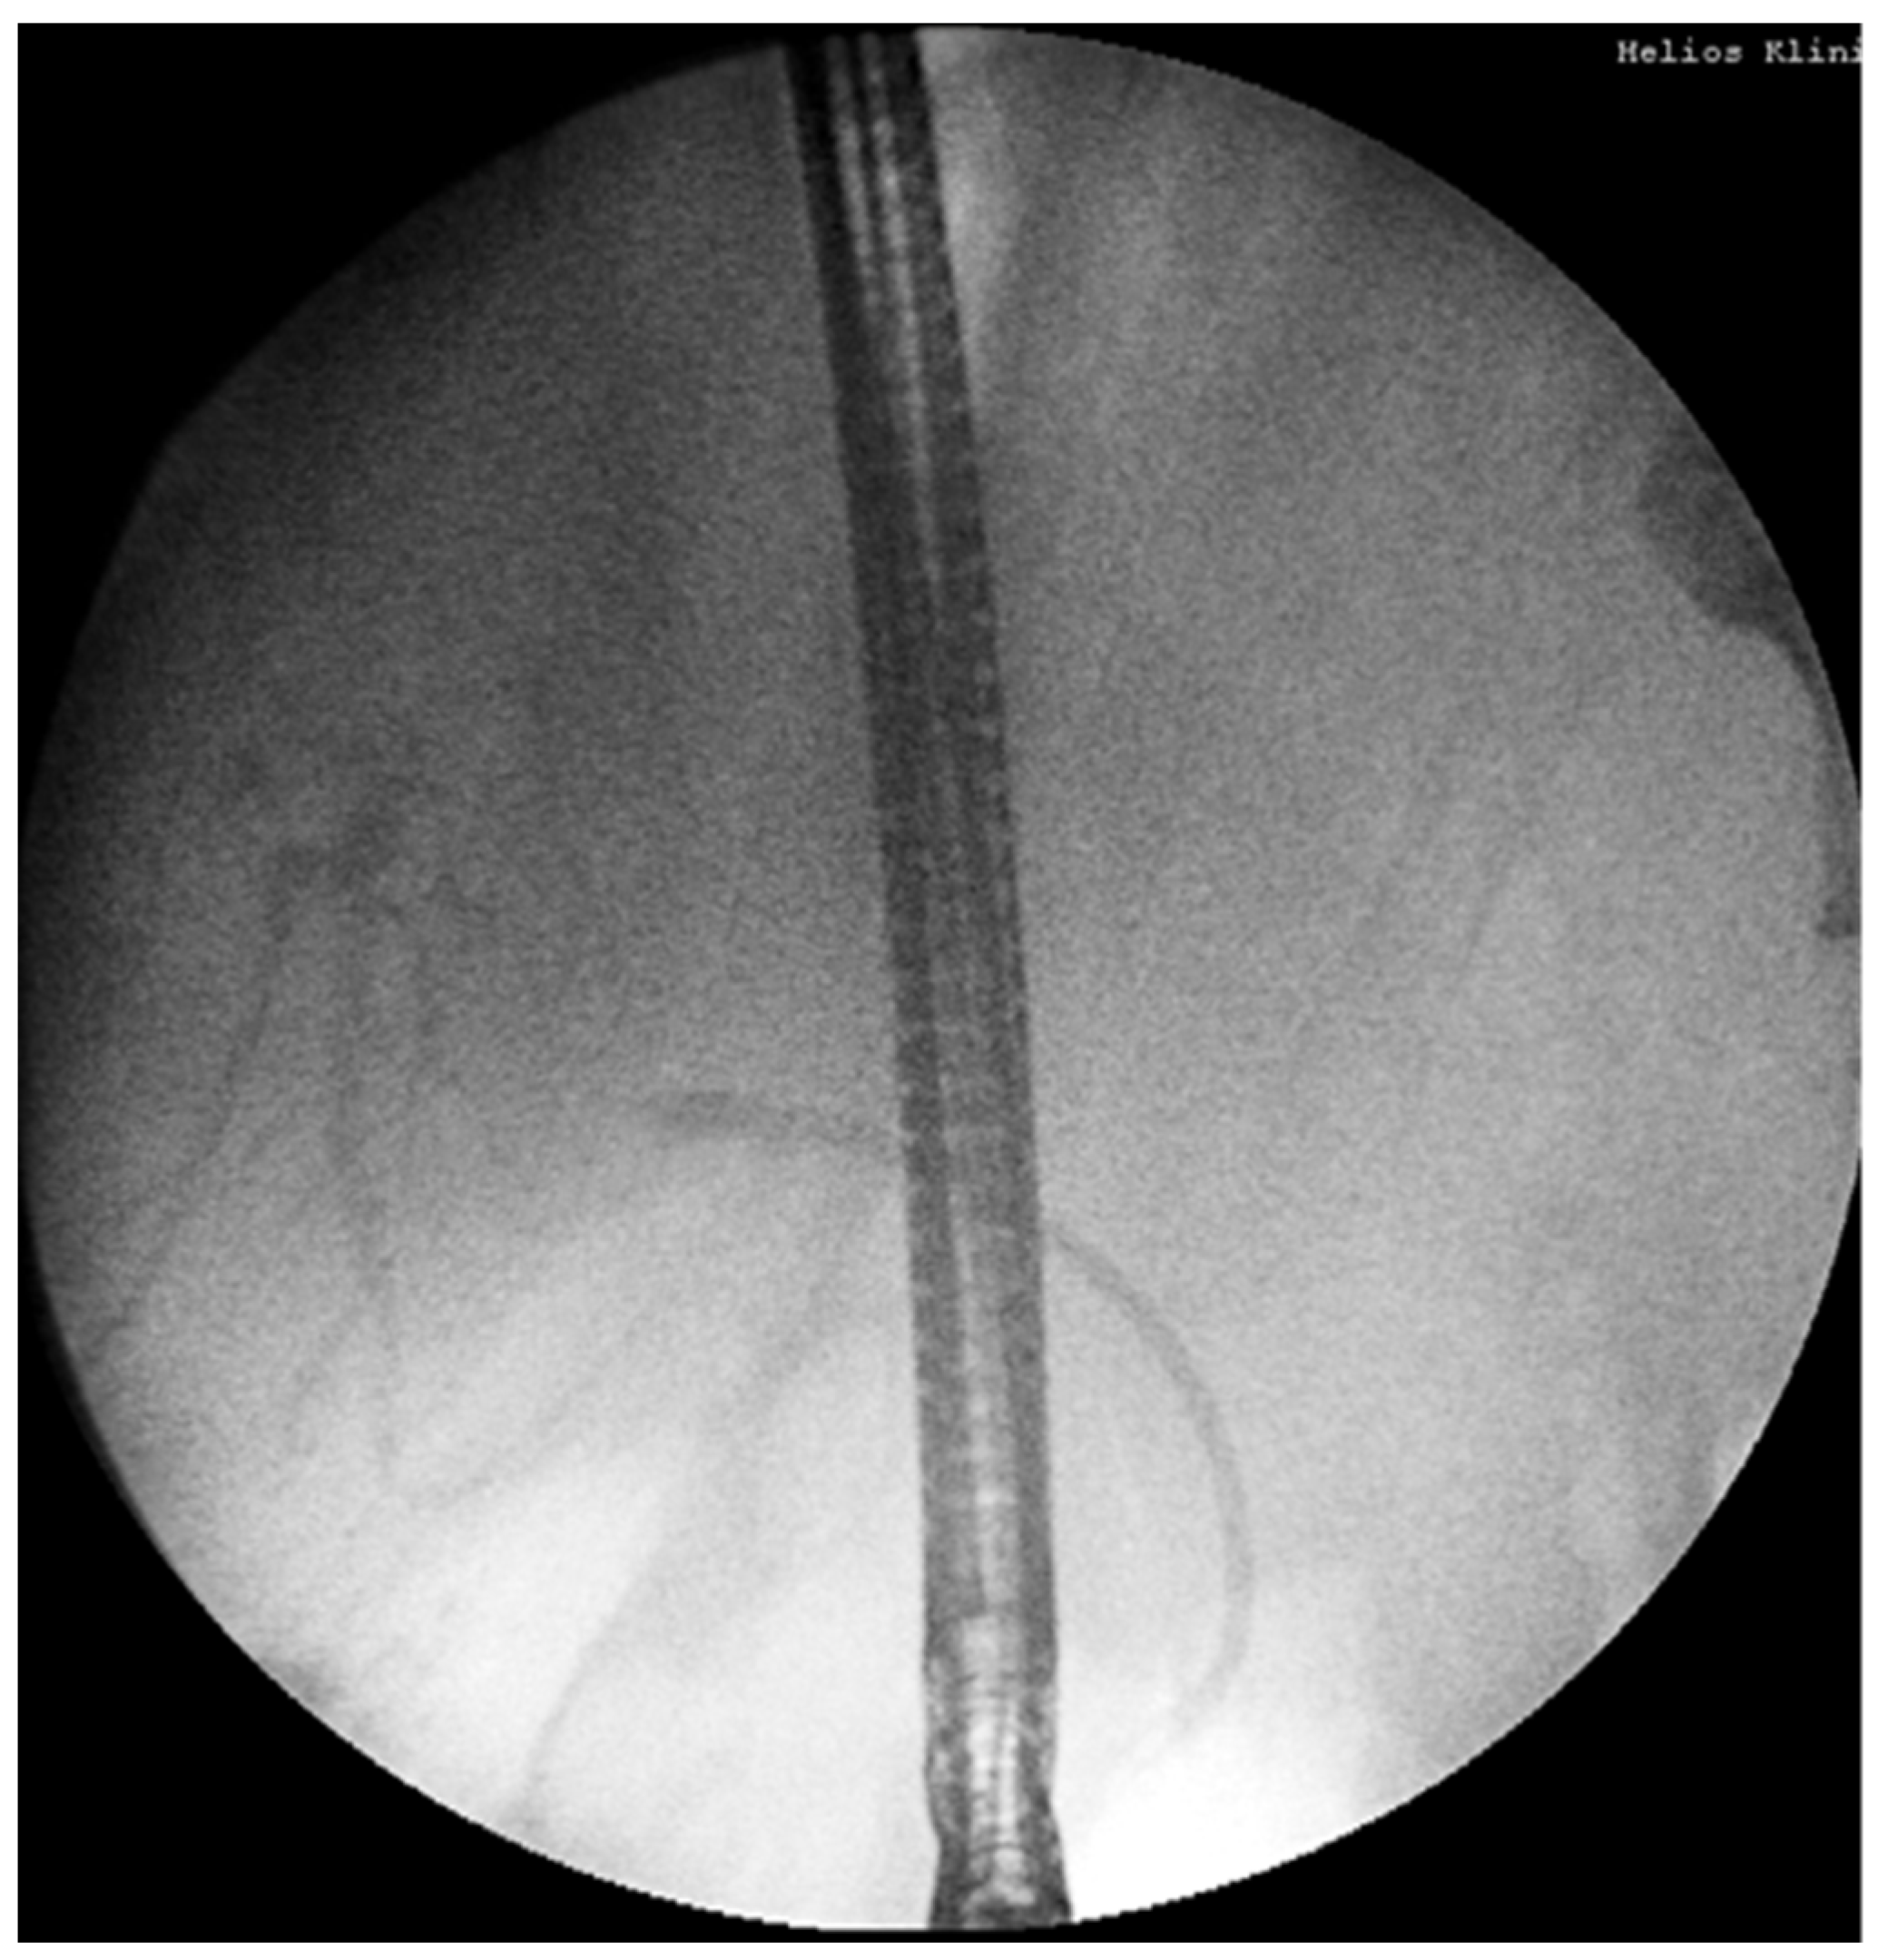

- 18.02: Second ERCP again found no obstructive lesion; a 10Fr/10cm plastic stent was placed empirically (Figure 2B). No clinical or biochemical improvement was observed.